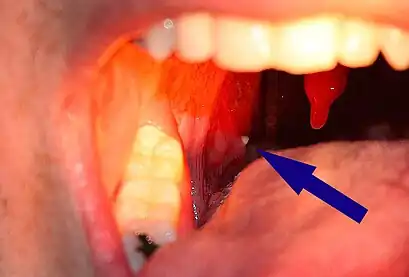

A tonsillolith protrudes from the tonsil- Large tonsillolith half exposed on tonsil

Much rarer than the typical tonsil stones are giant tonsilloliths. Giant tonsilloliths may often be mistaken for other oral maladies, including peritonsillar abscess, and tumors of the tonsil.[17] On average, tonsil stones should appear within a similar range of the image shown here; however, individuals with extenuating cases have been reported. In these instances, extensive care such as extraction by a licensed medical professional may be needed.